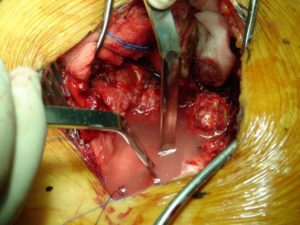

Στη δεύτερη φάση που πραγματοποιήθηκε μετά από δύο ημέρες, κατόπιν προσθίας δεξιάς και αριστεράς οπισθιο-περιτοναϊκής προσπέλασης στη κοιλιακή χώρα, εγένετο παροχέτευση των προ-παρασπονδυλικών αποστημάτων. Δόθηκε υλικό από τους ιστούς και την πυώδη συλλογή για καλλιέργεια.

Εικόνα 5 (α,β)

- α

- β